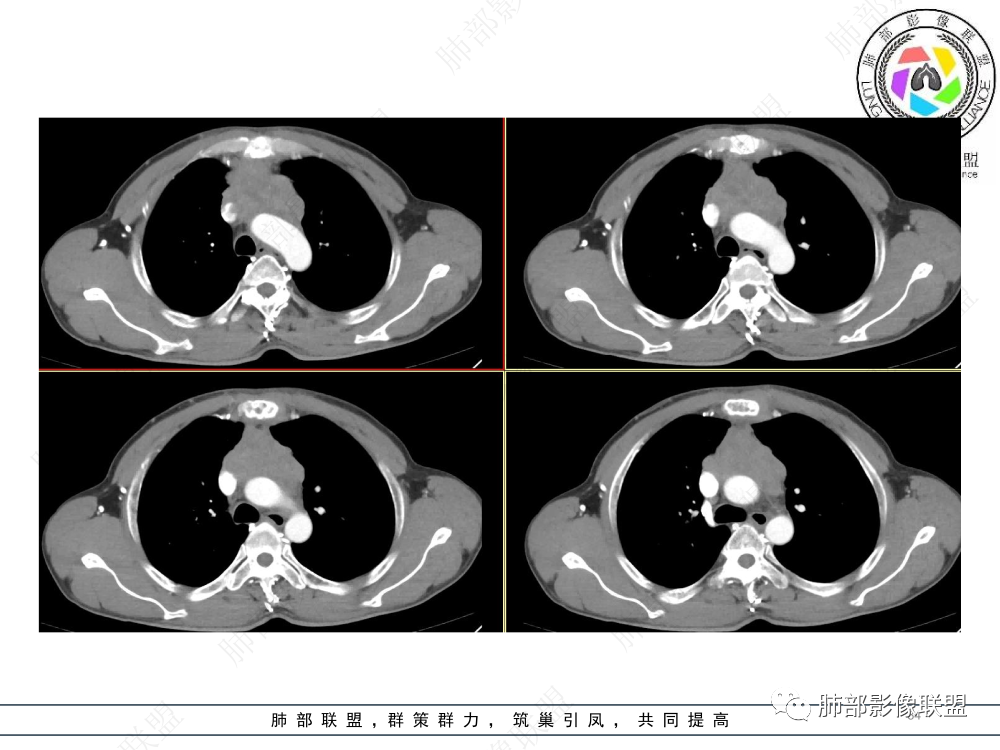

2.影像表现:前上纵隔较大肿块,密度不均,形态不规则,边界不清,有结节样突起,脂肪间隙显示不清。病灶侵犯左无名静脉及上腔静脉,其中左无名静脉闭塞(胸背部侧支循环明显,亦表明回流受阻)。增强后轻中度不均强化。坏死边界欠清晰。可见心包积液,提示心包受侵犯。右侧上叶及纵隔胸膜下结节影,疑胸膜肺转移可能。胸骨柄后缘皮质不完整,疑骨质破坏(未提供骨窗及矢状位图像)。左锁骨上可见肿大淋巴结。

胸腺癌:病灶边界不清,骨骼及血管受侵破坏,胸膜、肺及心包受侵转移等首先想到胸腺癌。胸腺癌最常见病理类型为鳞癌,占70-79%。预后较差,50-65%初诊时伴肺转移,极少伴重症肌无力。影像:胸腺鳞癌形态不规则,易坏死,范围大,坏死区边缘常模糊。

淋巴瘤:体积常较大,常见常在10cm以上,相对低密度结节样堆砌感比较明显,对待骨骼、血管等结构相对“温和”,所谓“血管漂浮”、“肉包骨”则较为常见。病理类型几乎只见于:经典HD、大B细胞淋巴瘤,前驱T淋巴母细胞瘤。实验室检查LDH可升高。初诊时罕见钙化,罕见胸膜受侵。有坏死也常常边界清楚或呈囊变样外观,可伴纵隔、锁骨上淋巴结肿大。

神经内分泌肿瘤:包括不典型类癌,类癌,小细胞癌,大细胞神经内分泌癌。最常见“不典型类癌”,临床可伴发Cushing综合征,肿瘤体积往往较大,近半的病灶边界较清晰,骨转移以成骨常见,如发现胸椎的骨转移,要想到类癌可能。增强后可轻度、中等或显著强化。